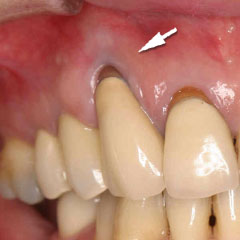

CTG ブラッシングで退縮した歯肉を小手術により元にもどしました。(術後3年半)

| 歯肉が薄いため退縮が起こってます。 | 小手術をして歯肉を厚くしました。 |